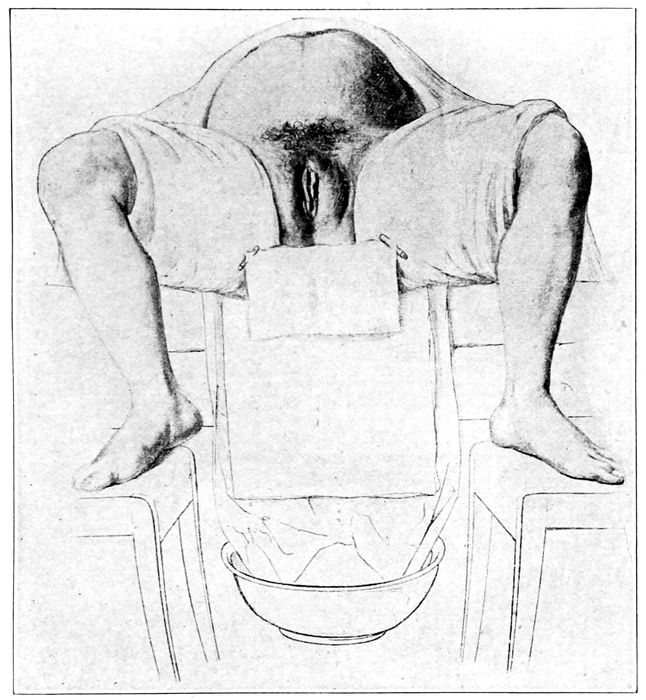

| 100. |

The knee-elbow posture |

236 |

| |

| 101. |

The knee-chest posture |

236 |